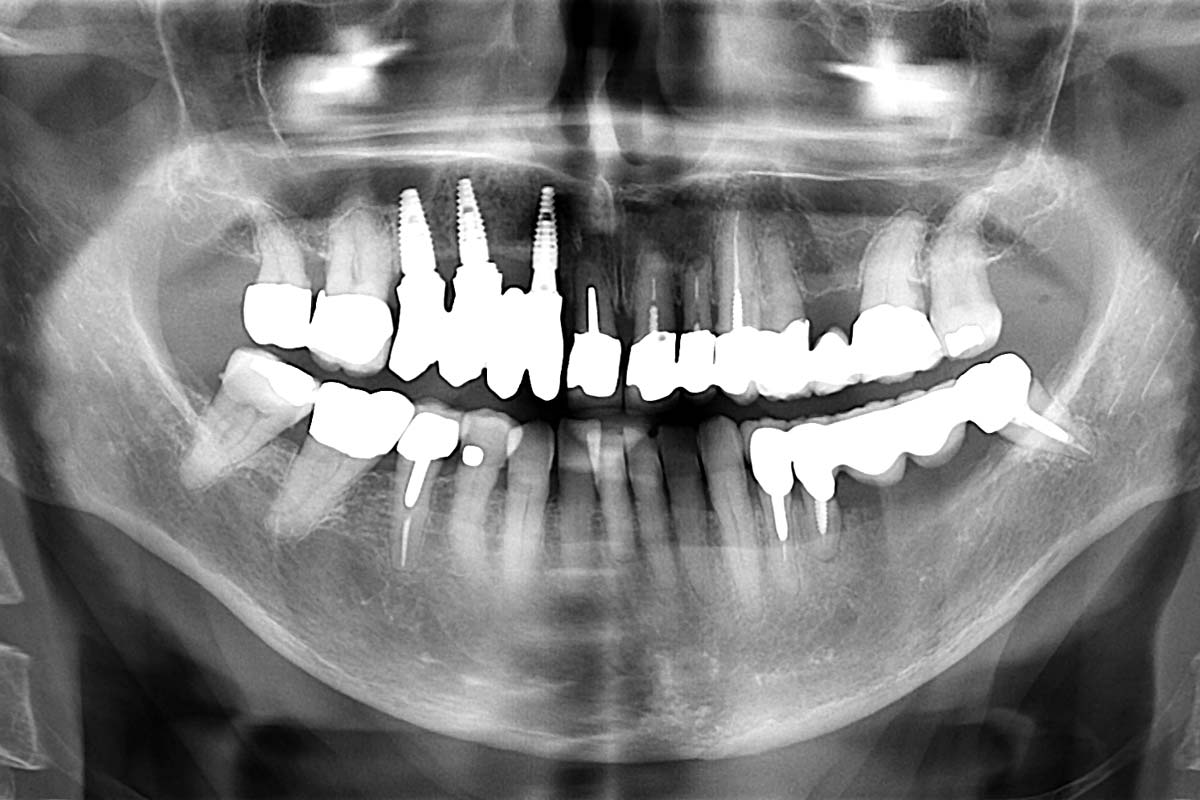

Initial x-ray, ten years post implantationem alio loco, large peri-implant bone loss